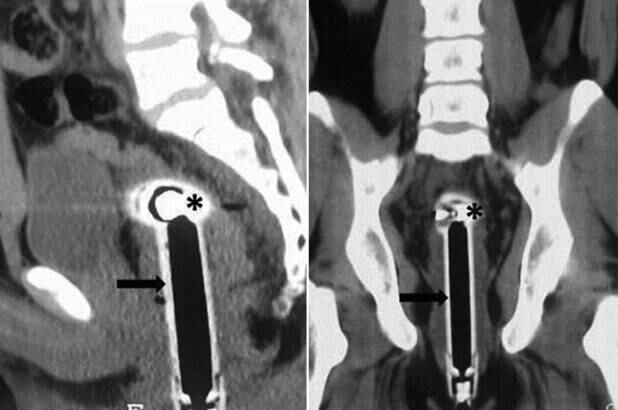

Quince centímetros medía el cuerpo extraño con el que un hombre de 26 años en India llegó al hospital. El sujeto, cuyo nombre no ha sido revelado, tenía en su recto una ducha teléfono y según dijo a los médicos, había llegado a ese lugar cuando “accidentalmente” resbaló en el baño.

El impactante caso fue documentado por los especialistas del hospital Ram Monohar de Nueva Delhi y publicado en el sitio de la Asociación Médica Británica (BMJ, por sus siglas en inglés), como objeto de estudio.

El caso del joven fue catalogado como “inusual” por los especialistas que detallaron que el paciente no tenía “signos de hemorragia activa ni peritonismo”.

“La extracción se realizó con éxito en el quirófano bajo anestesia general, con un período sin complicaciones posterior al procedimiento y el paciente fue dado de alta después de 48 horas de observación”.